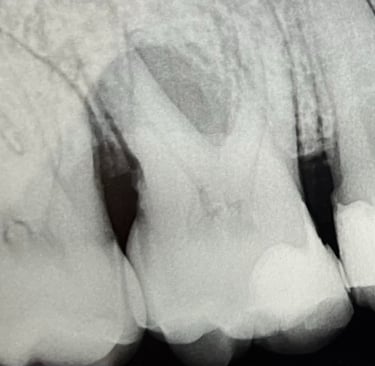

Il primo premolare superiore destro presenta una grave perdita ossea, visibile come un’area grigio scuro lungo il lato destro della radice. Le opzioni di trattamento consistono nel trattamento parodontale o estrazione del dente. A un anno dal trattamento rigenerativo parodontale, si osserva un netto miglioramento della situazione, con un evidente riempimento osseo attorno alla radice nella zona precedentemente compromessa.